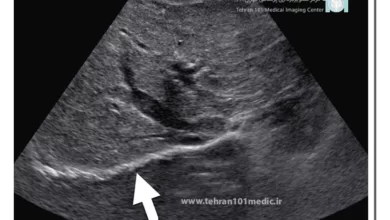

سونوگرافی شکم و لگن یک نوع تصویربرداری غیرتهاجمی است که از امواج اولتراسوند برای ایجاد تصاویری از اندامها و ساختارهای داخل شکم و لگن استفاده میکند. این روش برای بررسی دقیق ساختار، شکل داخلی و عملکرد اندامهایی مانند کیسه صفرا، کبد، کلیه، مثانه، دیواره رحم، تخمدان، بافتهای نزدیک لگن و … به کار میرود. این روش به منظور بررسی دقیق ساختار، شکل داخلی و عملکرد اندامهای داخل شکم و لگن انجام میشود و میتواند به تشخیص مشکلات مانند تومور، کیست و عفونت کمک کند.